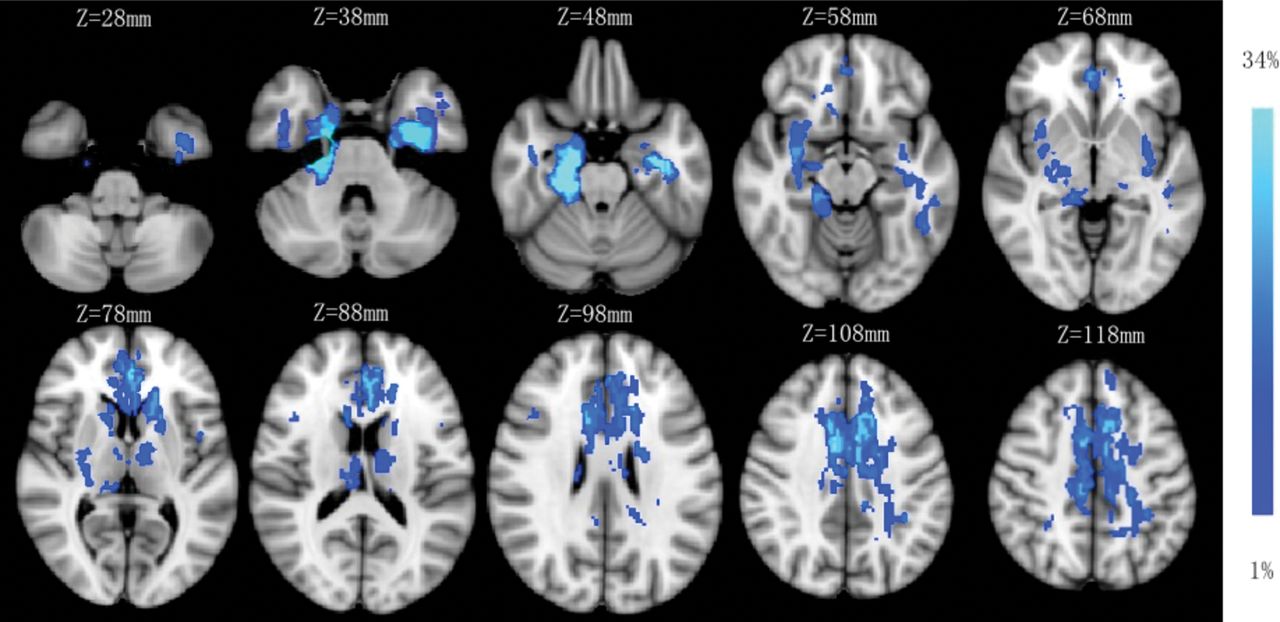

Twenty-eight (28/53, 53%) patients with anti-NMDA receptor encephalitis had normal MR imaging (type 1) results at the onset phase, and 25 patients (25/53; 47%) presented with abnormal MR imaging results—type 2: seven patients (7/25, 28%) with lesions in the hippocampus only; type 3: seven patients with lesions in the frontal lobe (n = 3); cingulate gyrus and middle cerebellar peduncle (n = 2); and corpus callosum, insula, basal ganglia, thalamus, and brain stem (n = 1), without hippocampal lesions; and type 4: 11 patients (11/25, 44%) with lesions in both the hippocampus and other brain areas, including the frontal lobe and temporal lobes (n = 8); parietal lobe (n = 5); thalamus (n = 3); basal ganglia, cingulate gyrus, and brain stem (n = 2); and insula, occipital lobe, corpus callosum, and internal capsule (n = 1). One patient had only limbic lesions among 18 patients in types 3 and 4. The sample images of the 4 MR imaging types are shown in Fig 1, and the lesion probability map is shown in Fig 2. Normal brain MR imaging results were observed more frequently in female patients (19 of 28, 68%) than in male patients (9 of 25, 36%) (P = .020). No difference was observed in brain MR imaging manifestations between age groups (pediatric versus adult groups) (P = .982).

Lesion probability map of brain MR imaging. The mean lesion probability distribution thresholded at 34% is shown in light blue and thresholded at 1% is shown in blue and overlaid on the ICBM152 T1 template in the Montreal Neurological Institute space.